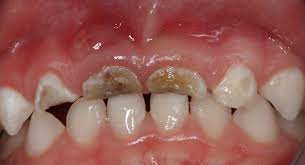

Dental Caries: A microbial-driven, multifactorial disease that leads to the demineralization and destruction of dental hard tissues, primarily caused by acidogenic bacteria such as Streptococcus mutans. Visually, it appears as darkened pits or lesions on enamel surfaces, often found in occlusal or interproximal areas (Fig. 1(b)).

(b) Caries